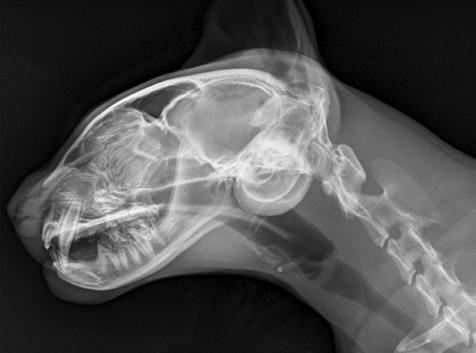

1. Radiografías de la cabeza de un gato maine coon de un año de edad. (A) Proyección lateral. (B) Proyección dorsoventral. (C) Rostro 10º ventrodorsocaudal oblicua.

Se presentó en consulta un gato macho castrado de raza maine coon, de un año de edad y 5,8 kg de peso, remitido con historia de otitis externa desde hacía un mes.

En la exploración otológica se visualizó una masa en el conducto auditivo externo izquierdo, apreciable desde la abertura del pabellón auricular. La masa era sólida, poco móvil y obstruía totalmente el canal auditivo. El resto del examen físico y pruebas de enfermedades víricas fueron normales. En el análisis sanguíneo se evidenció neutrofilia con desviación a la izquierda y trombocitosis.